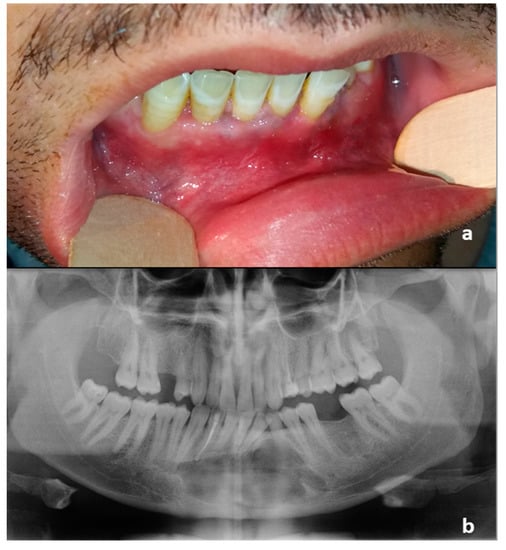

Figure 4.

(a) Intraoral preoperative picture. The fistula was not noticeable after antibiotic therapy. No ulceration of the oral mucosa was detectable; (b) Orthopantomography following the diagnostic biopsy and lower canine extraction.

In our case, there was a 10-year diagnostic delay that has led to recurrent purulent discharge from an oral fistula, no more noticeable after antibiotic therapy at the moment of PIOSCC diagnosis (Figure 4a).